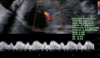

Nome desse achado?

Incisura proto-diastólica

126

Alteração + grave desse Doppler

Onda A reversa

Achado?

Diástole zero